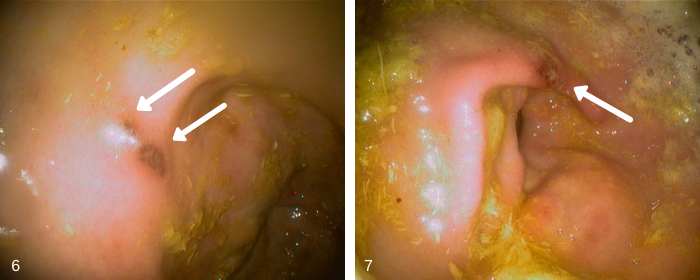

Images 6 & 7 – These 2 pictures are of a single focal area of moderately severe glandular ulcer near the closeding of the pylorus. This horse showed signs of aggression when being saddled and was cranky at work. No weight loss or inappetence noticed.